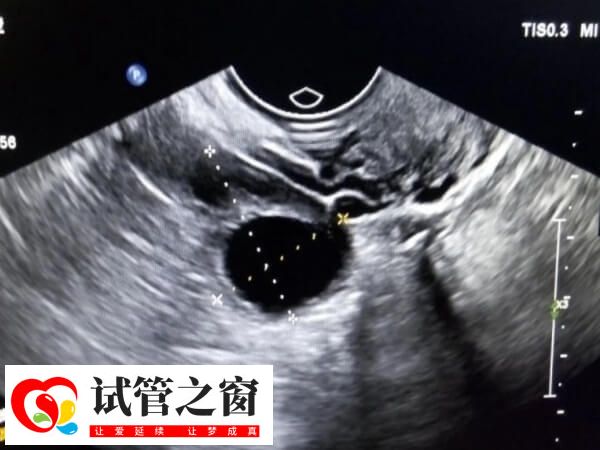

促排卵期间将持续进行卵泡监测。当卵泡发育到一定程度,医生会安排取卵手术,同时需要取出男性精子,费用大概在5000-10000元。